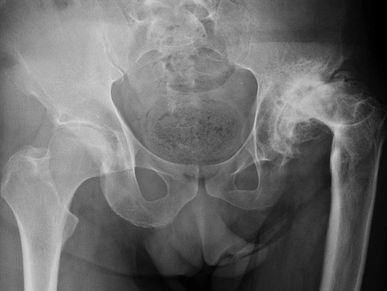

Mirá cómo recuperamos la movilidad en un caso de artrosis severa y deformidad acetabular mediante tecnología 3D de alta precisión. Planificación preoperatoria en 3D para cirugía de cadera con artrosis severa e importante deformidad acetabular. Se imprimieron biomodelos en 3D y guías para la correcta colocación de los componentes protésicos. De esta manera, se logró restaurar la longitud de las piernas y se eliminó el dolor invalidante que presentaba el paciente.

Paciente con artrosis severa y deformidad ósea que dificultaba la colocación acetabular. Con tomografía realizamos planificación 3D y diseñamos una guía quirúrgica personalizada impresa en 3D. En quirófano replicamos el plan: posicionamiento preciso del componente y restauración del centro de rotación. La tecnología 3D aporta más precisión, seguridad y predictibilidad en casos complejos.